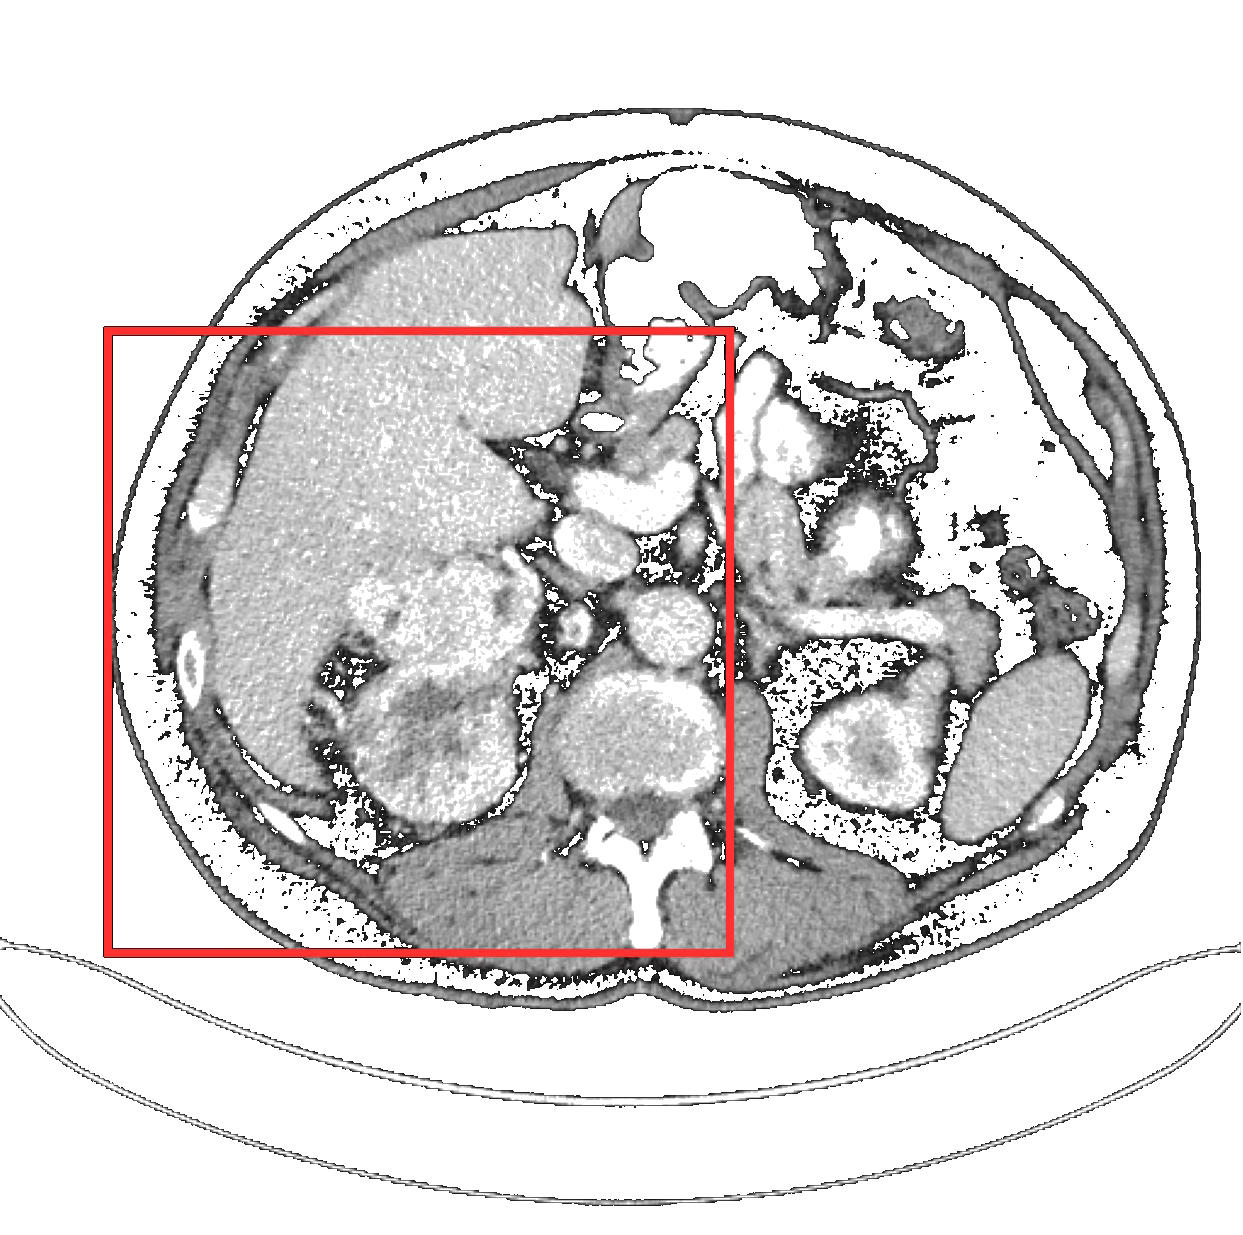

CT Scan AI Analysis

TendersLab developed a state-of-the-art End-to-End (E2E) Deep Learning system serving as a high-fidelity Clinical Decision Support System (CDSS). The model rapidly identifies and classifies kidney tumors as benign or malignant with exceptional accuracy, empowering diagnosing physicians with data-driven insights.

Built as a robust proof-of-concept utilizing a public dataset of 600 CT scans. The E2E architecture bypasses manual segmentation entirely, vastly reducing processing time and human error.